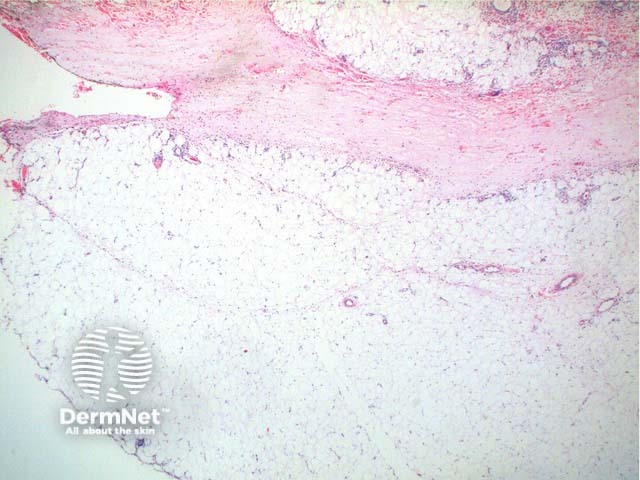

Scanning power view of Wells syndrome reveals a superficial and deep perivascular and interstitial inflammatory pattern (Figures 1 and 2). This can be seen to extend into the subcutaneous tissue (Figure 3) or even the underlying muscle. The inflammatory infiltrate is comprised of lymphocytes, histiocytes and abundant eosinophils (Figures 4,5 and 6). Degranulation of the eosinophils is seen forming flame figures (Figures 4 and 5). In this particular case extensive interstitial mucin is seen (Figures 4 and 5).

Figure 3